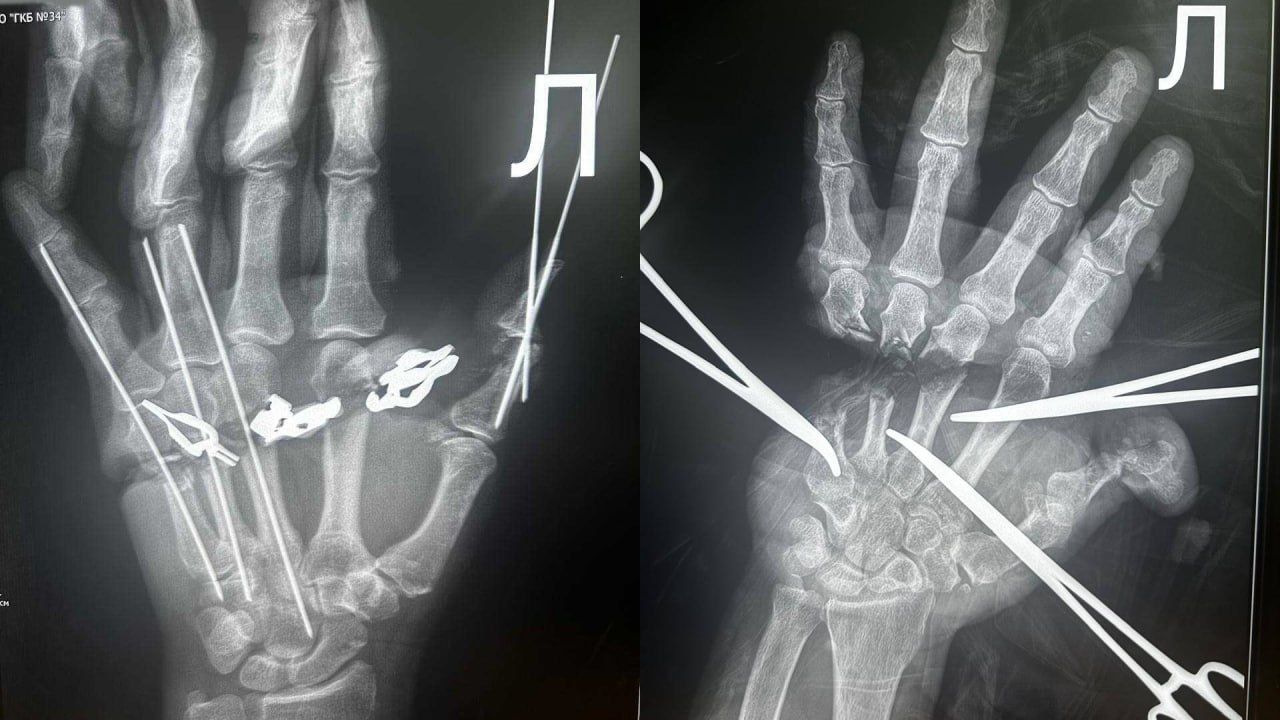

Врачи пришили новосибирцу отрезанную кисть.

Мужчина покалечил сам себя во время работы. Тут же вызвали врачей, через 18 минут пациент был в ГКБ № 34 — началась сложнейшая операция.

Специалисты восстановили сосуды, нервы, сухожилия и кости. Спустя несколько часов конечность собрали заново. Есть все шансы, что кисть у работяги будет работать как надо.